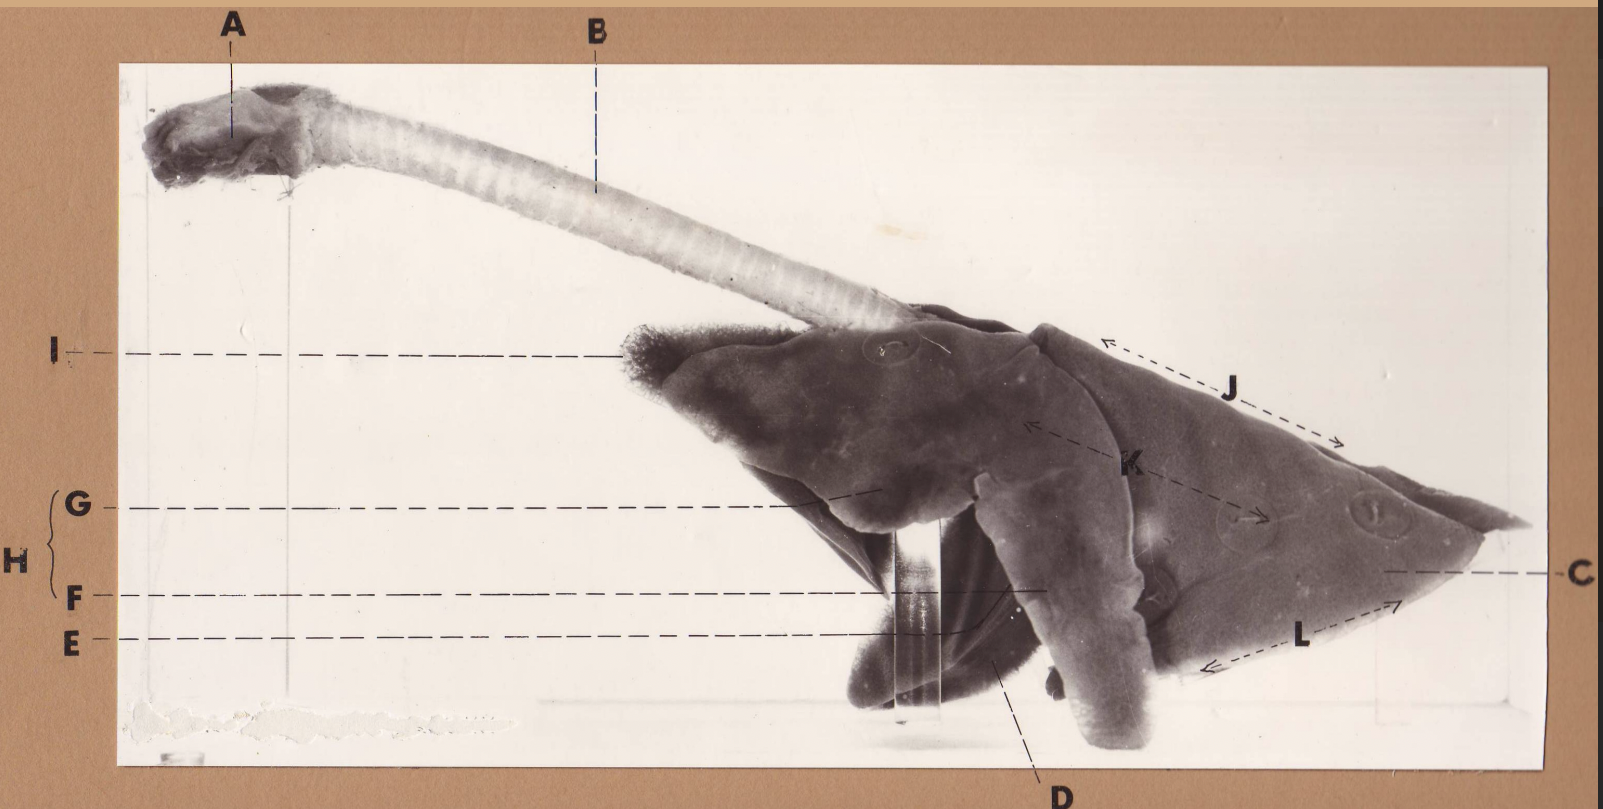

A

(cat larynx/trachea/lungs, L lateral)

larynx

B

(cat larynx/trachea/lungs, L lateral)

trachea

C

(cat larynx/trachea/lungs, L lateral)

caudal lobe

D

(cat larynx/trachea/lungs, L lateral)

middle lobe

E

(cat larynx/trachea/lungs, L lateral)

cardiac notch

F

(cat larynx/trachea/lungs, L lateral)

caudal segment, cranial lobe

G

(cat larynx/trachea/lungs, L lateral)

cranial segment, cranial lobe

H

(cat larynx/trachea/lungs, L lateral)

cranial lobe

I

(cat larynx/trachea/lungs, L lateral)

apex

J

(cat larynx/trachea/lungs, L lateral)

dorsal border

K

(cat larynx/trachea/lungs, L lateral)

costal surface

L

(cat larynx/trachea/lungs, L lateral)

basal border